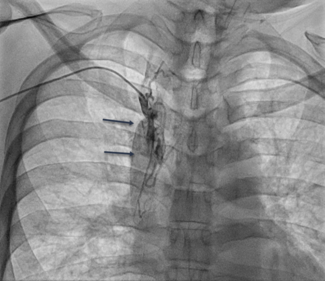

In this retrospective study, the authors aimed to determine whether subclavian/innominate venoplasty allows successful right heart catheterization in patients with subclavian/innominate vein stenosis .